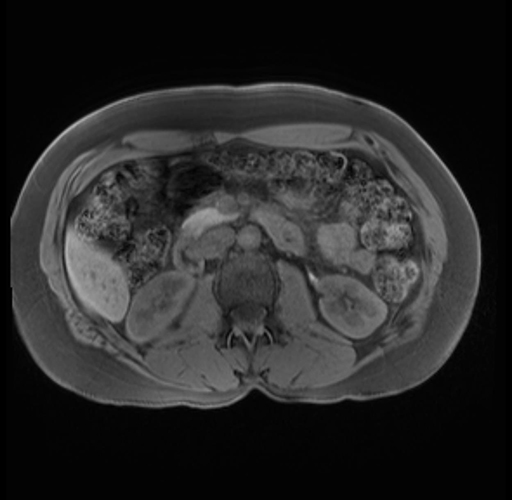

Imaging Analysis

Look through the patient's CT scan to identify any areas of concern for the necessary procedure.

Based on your CT findings, which issue(s) are present and would give reason for "planned slowing down moment(s)" in this case?